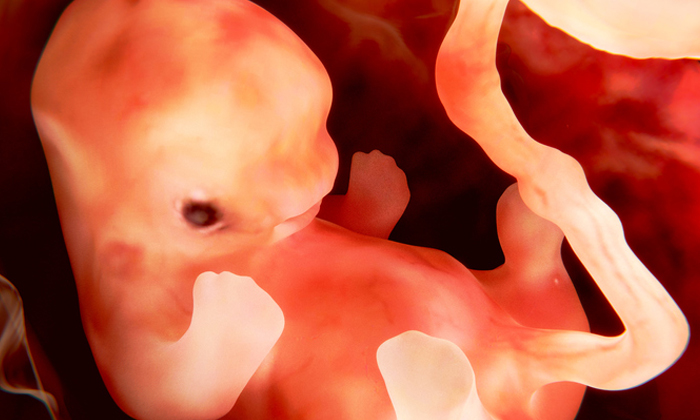

తల్లి కడుపులో బిడ్డ తొమ్మిది నెలలు ఉంటాడు/ఉంటుంది అని మనకు తెలుసు.అక్కడే ఆక్సిజన్, అక్కడే నిద్ర .ఇంతేనా? బిడ్డ నుంచి ఇంకా ఎలాంటి స్పందనలు, ప్రతిస్పందనలు ఉండవా? ఎందుకుండవు ఉంటాయి.అందులో కొన్ని నవ్వు తెప్పిస్తాయి, మరికొన్ని భయాన్ని కలిగిస్తాయి.

మరి ఆ వింతలేంటో చూద్దాం.

* మూడు నెలలు దాటాక పసికందు కలలు కూడా కంటుంది తెలుసా? వినడానికి వింతగా అనిపించవచ్చు కాని ఇదే నిజం.తల్లి కడుపులో కలలు కనే ఎబిలిటి పిల్లలకి ఉంటుంది.కాని ఈ ప్రపంచాన్ని చూడని పిల్లలు ఏం కలలు కంటారు అనేది ఇప్పటివరకు శాస్త్రవేత్తలకి అంతుచిక్కట్లేదు.

* తల్లి తుమ్మినప్పుడు బిడ్డ చిన్నిపాటి ఆందోళనకు గురవుతుంది అంట.కాసేపు ఏం జరిగిందో, తల్లి శరీరం ఎందుకు కంపించినట్టు అయ్యిందో బిడ్డకు అర్థం కాదు.

* పెద్ద పెద్ద శబ్దాలు, ఎవరైనా గట్టిగా అరవడం, సినిమా థియేటర్లో సౌండ్స్ కావచె, ఇలాంటి శబ్దాలు విన్నప్పుడు కూడా బిడ్డ భయపడుతుంది.

* కడుపులో బిడ్డ తల్లి ద్వారానే ఆక్సిజన్ కూడా తీసుకుంటుంది.కాబట్టి తల్లి మంచి గాలి పీల్చుకోవాలి.సిగరేట్ వాసన వచ్చిన బిడ్డ ఇబ్బందిపడుతుంది తెలుసా.

* కడుపులో బిడ్డ ఆవలింత తీసుకుంటుంది తెలుసా. నిద్ర వలనో, బోర్ కొట్టడం వలనో కాని, బిడ్డ ఆవలింత కూడా తీసుకుంటుంది అంట.

* పసిబిడ్డకి ఎక్కిళ్ళు కూడా వస్తాయి.అలా వచ్చినప్పుడు తల్లికి తెలుస్తుంది అంట కూడా.